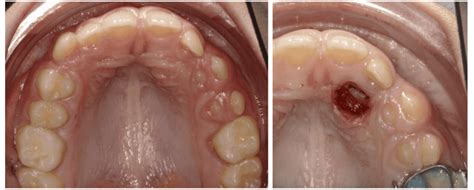

Caso. Caninos impactados.

El ortodoncista dispone de una variedad de opciones terapéuticas, pero para lograr el éxito es indispensable diagnosticar la impactación dentaria de manera oportuna.

El tratamiento ortodóncico-quirúrgico es una opción para la corrección de las impactaciones dentales. Es importante realizar un adecuado diagnóstico y tratamiento de los dientes retenidos evitando posteriores complicaciones funcionales y estéticas que puedan comprometer la integridad de las arcadas así como el desarrollo psicosocial del paciente. Se debe realizar un trabajo multidisciplinario evaluando la pieza impactada y tener un seguimiento hasta que ésta se encuentre incorporada a la arcada.

La fenestración de canino es un procedimiento quirúrgico que consiste en exponer la corona del diente retenido para permitir su correcto posicionamiento mediante ortodoncia. Esta técnica se realiza bajo anestesia local y sigue los siguientes pasos:

- Localización del diente retenido mediante radiografías o tomografías (CBCT) para determinar su posición exacta.

- Incisión en la encía y eliminación de tejido óseo que recubre la corona del canino.

- Colocación de un anclaje ortodóntico en el diente expuesto para guiarlo hacia su posición correcta.

- Cuidado postoperatorio y seguimiento ortodóntico, para asegurar una erupción controlada sin complicaciones.